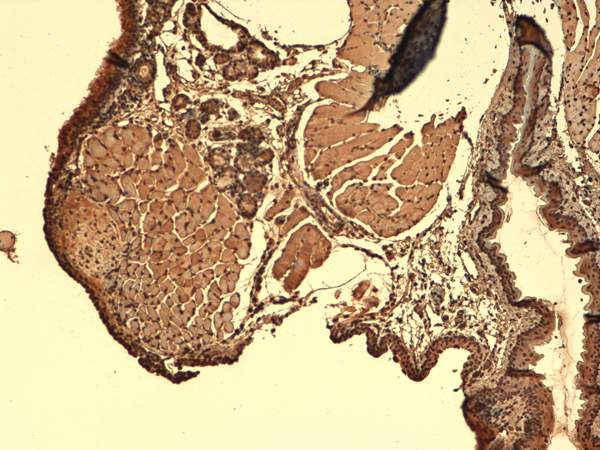

IHC (Immunohistochemisry)

(Immunohistochemistry analysis using Mouse Anti-Sodium Iodide Symporter Monoclonal Antibody, Clone 14F. Tissue: Trachea. Species: Mouse. Fixation: 10% Formalin Solution for 12-24 hours at RT. Primary Antibody: Mouse Anti-Sodium Iodide Symporter Monoclonal Antibody at 1:1000 for 1 hour at RT. Secondary Antibody: HRP/DAB Detection System: Biotinylated Goat Anti-Mouse, Streptavidin Peroxidase, DAB Chromogen (brown) for 30 minutes at RT. Counterstain: Mayer Hematoxylin (purple/blue) nuclear stain at 250-500 ul for 5 minutes at RT.)